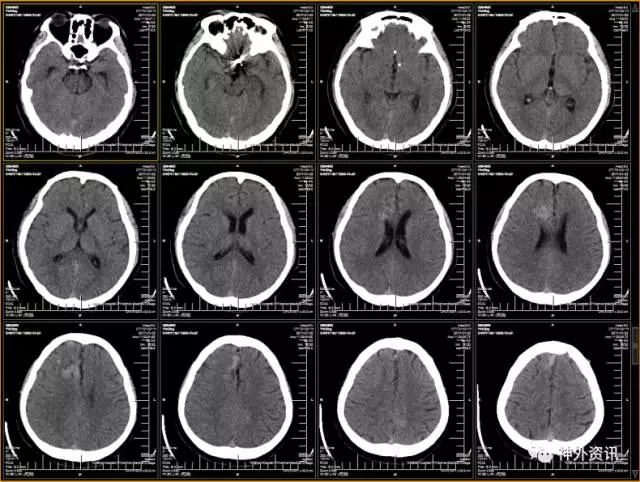

(术后头颅CT)

(术后10日头颅CT)

(术后头颅CT)